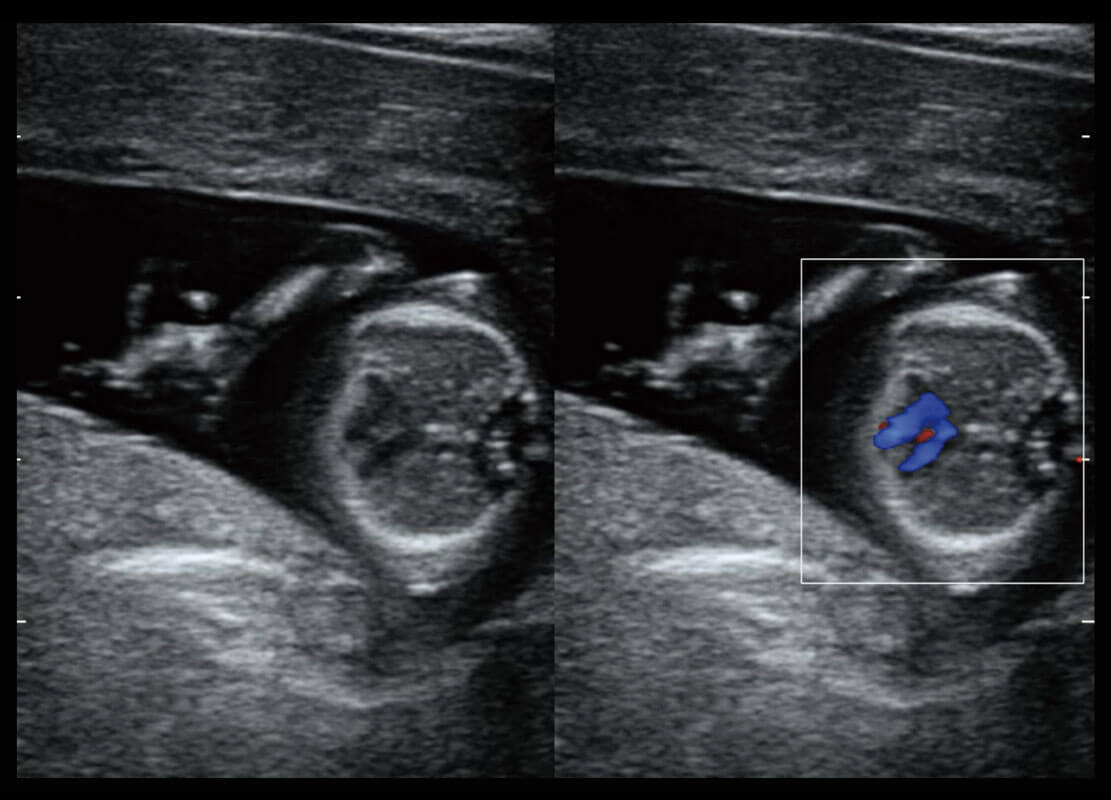

P60搭载一系列胎儿心脏成像技术,实现精细的胎儿心脏评估。

四腔心血流

右室双出口